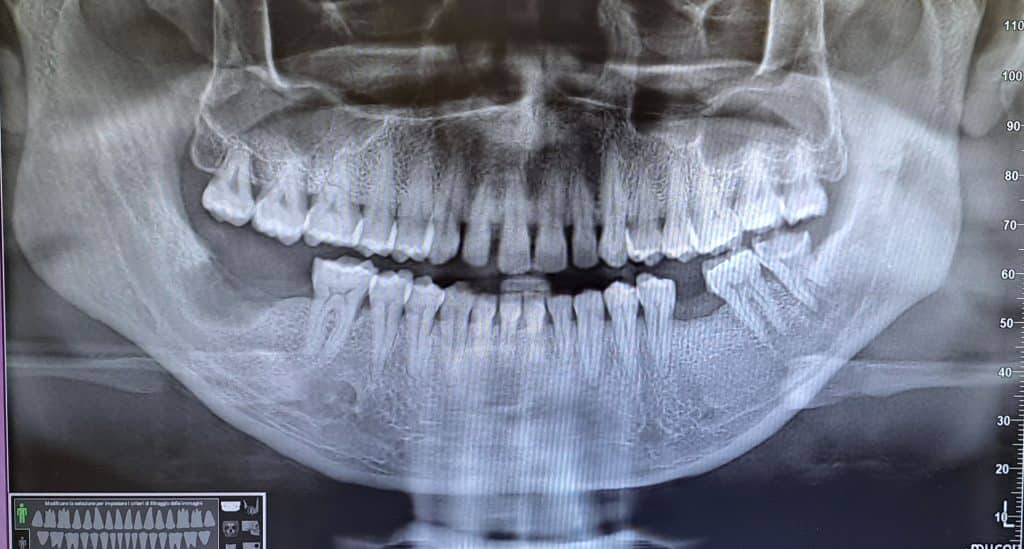

Si procede ad eseguire l’OPT dove si evidenzia Infezione apicale e si opta per l’estrazione dell’elemento dentario.